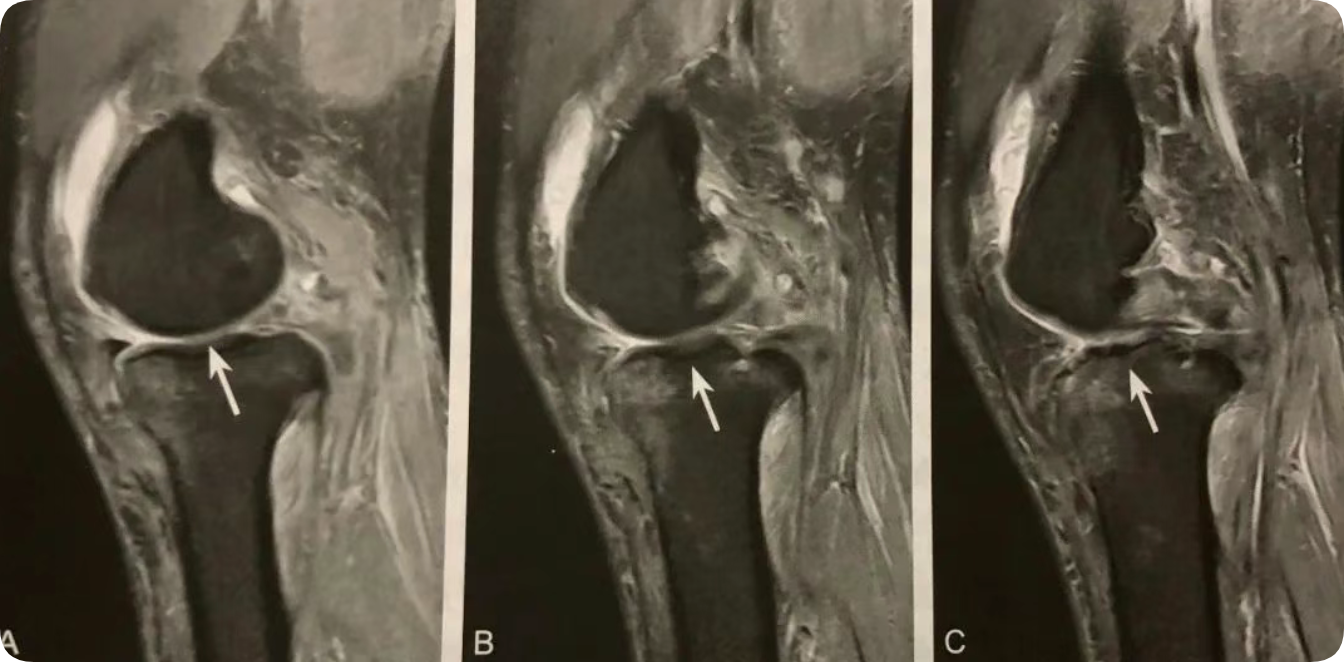

1. 主要位于半月板前角边缘和关节囊之间;

2. 在膝关节侧位片或 MRI 矢状位观察;

3. T1WI 稍低或低信号;

4. T2WI 脂肪抑制呈高信号;

5. 增强扫描病变无强化或边缘轻度强化。